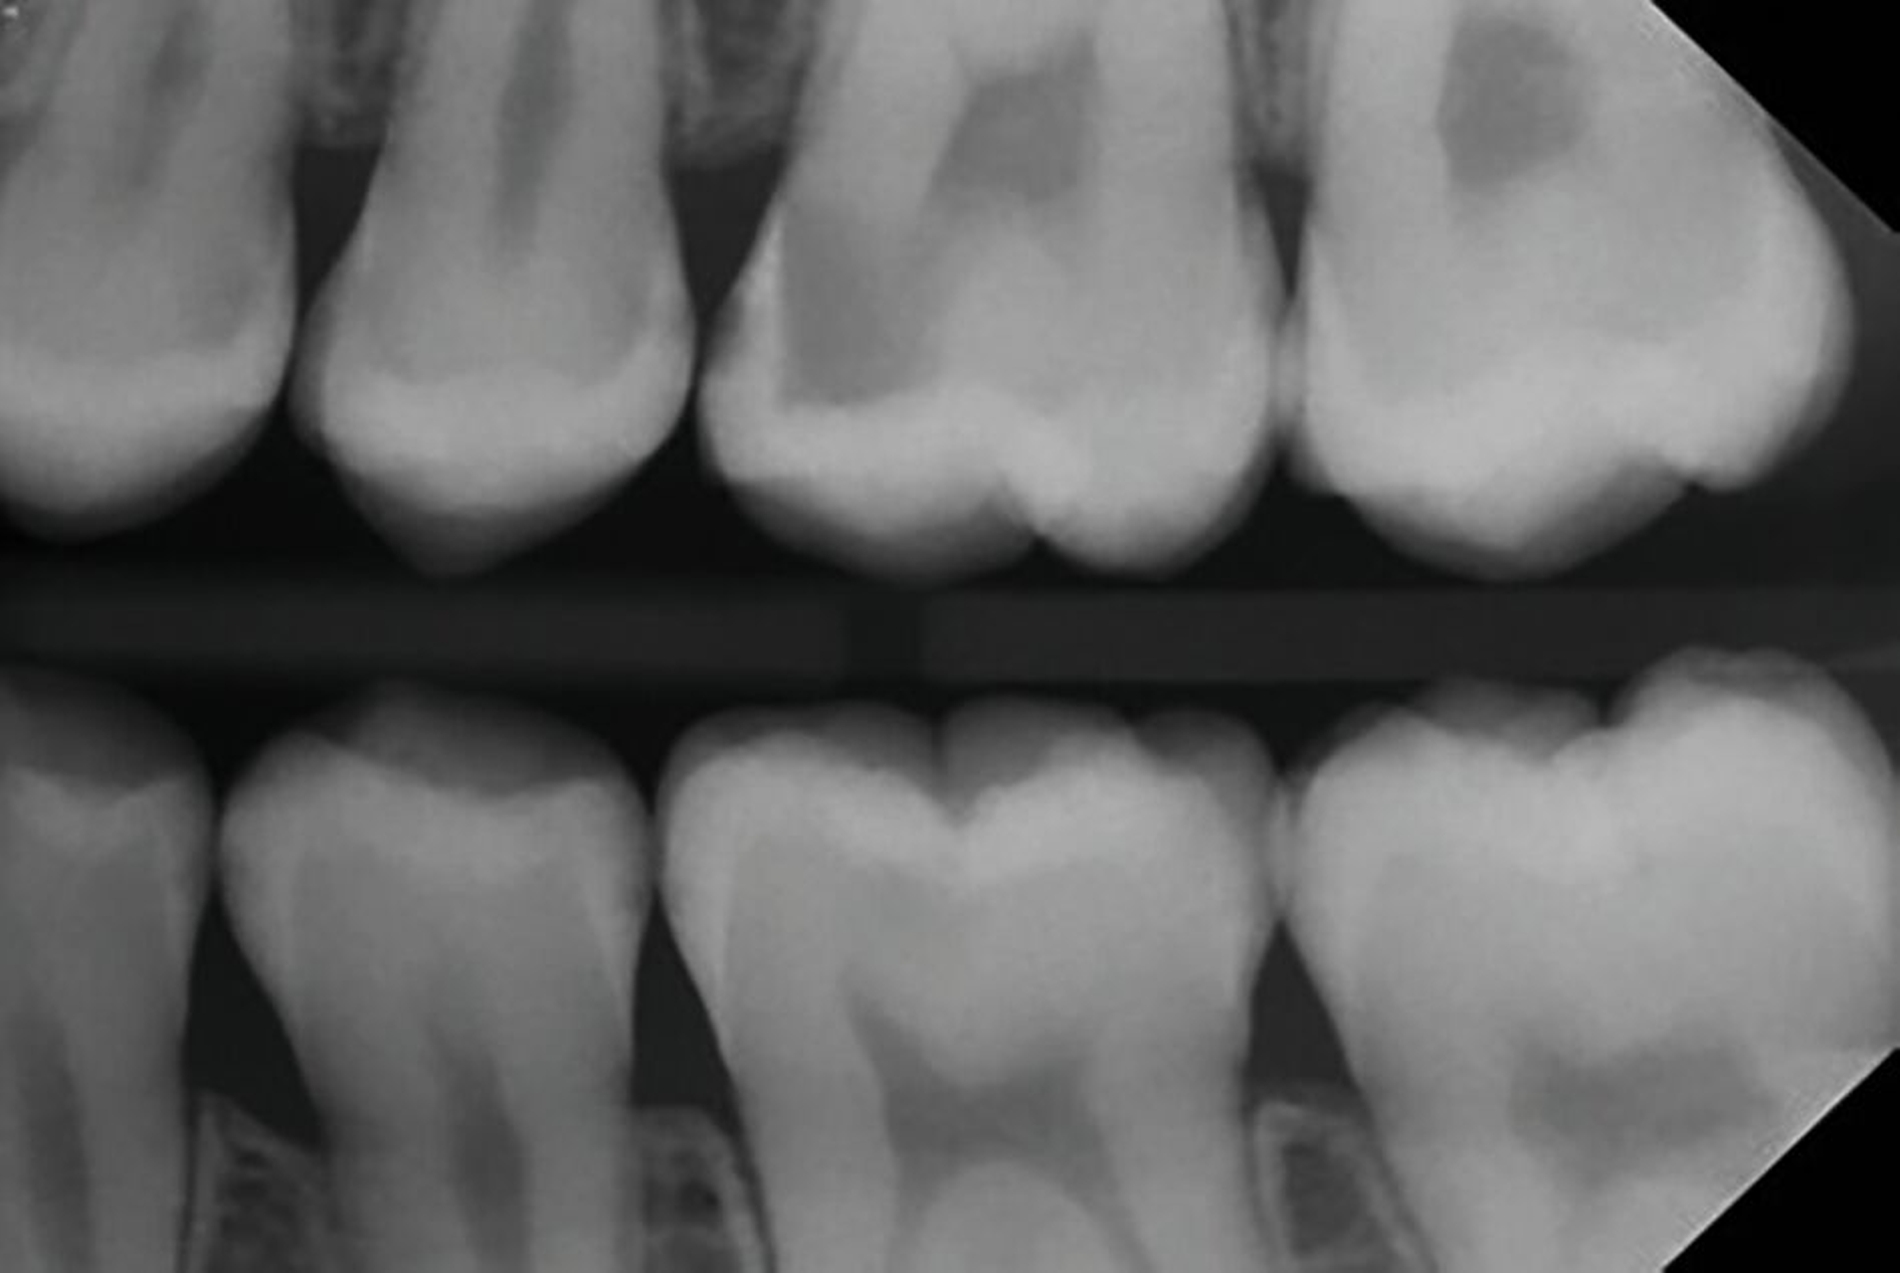

Der verkürzt dargestellte Patientenfall zeigt dieses minimalinvasive, innovative und kostengünstige Behandlungskonzept [Ahmed et al., 2023]. Im Kern werden dazu nach vorheriger Diagnostik orthodontische Separiergummis in die Zahnzwischenräume eingesetzt und für circa ein bis zwei Stunden in situ belassen. Direkt nach der Entfernung der Gummis erfolgt eine zügige, direkte klinische Untersuchung der Approximalkaries und eine Applikation von SDF zur Kariesinaktivierung mittels Microbrush.

Der Patientenfall belegt röntgenologisch die hohe Kariesaktivität vor der Behandlung, sowie die deutlich reduzierte Kariesaktivität nach der einmaligen SDF-Applikation in der oben genannten Technik nach knapp eineinhalb Jahren anhand von Bissflügelaufnahmen (Abbildungen 8a bis 8g). Eine retrospektive Pilot-Untersuchung an der Kinderzahnheilkunde in Greifswald gibt deutliche Hinweise auf die Wirksamkeit dieser Technik. Die Ergebnisse wurden beim diesjährigen Weltkarieskongress vorgestellt und diese Studie wurde ebenfalls von ORCA prämiert. Die Ergebnisse dieses Pilotprojekts zeigen für gut 90 Prozent der behandelten E1/E2/D1-Läsionen über einem Zeitraum von 15 Monaten keine weitere Progression in den Bissflügelaufnahmen [Ahmed et al., 2024].